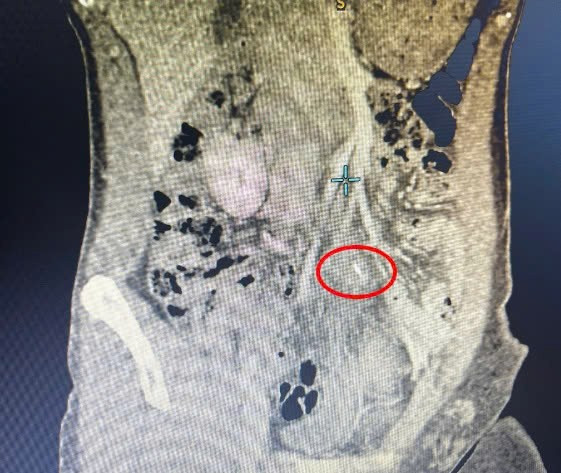

Sau đó, bệnh nhân đến khám tại Phòng khám Ngoại Tổng quát – Bệnh viện Đa khoa (BVĐK) Xuyên Á Vĩnh Long. Tại đây, bác sĩ chỉ định chụp MSCT bụng có tiêm thuốc cản quang để đánh giá chính xác tình trạng. Kết quả ghi nhận có dị vật vùng hạ vị, nghi ngờ xuất phát từ ruột non, kèm ổ áp xe, nên bệnh nhân được chỉ định phẫu thuật.

Hình ảnh xương cá đâm thủng ruột non trên phim chụp - Ảnh BVCC

Bệnh nhân được gây mê nội khí quản. Các bác sĩ tiến hành nội soi ổ bụng qua 3 vết mổ nhỏ, mỗi vết chỉ khoảng 0,5cm. Qua thăm dò, ê-kíp phát hiện dị vật là một chiếc xương cá dài khoảng 3cm đã xuyên qua thành ruột non và đâm vào thành bụng vùng hạ vị, tạo thành ổ áp xe mủ kích thước khoảng 5x5cm.